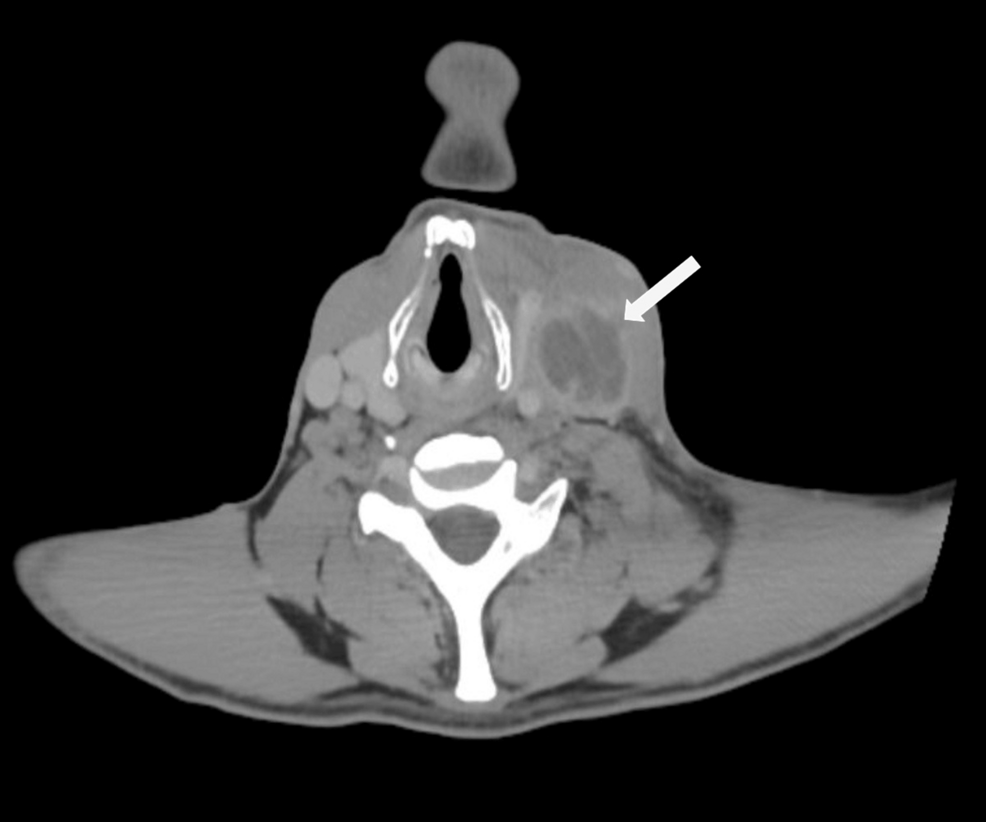

The Cureus case report specifically focuses on a recurrence presenting with extensive CVST – a particularly dangerous complication. CVST occurs when blood clots form in the venous sinuses of the brain, potentially leading to stroke, neurological deficits, and even death. The link between Lemierre’s and CVST is well-established, but recurrent cases with such severe thrombotic events raise questions about long-term vascular damage and the effectiveness of current anticoagulation strategies. The challenge lies in identifying patients at high risk for CVST recurrence and tailoring treatment accordingly.

Early and accurate diagnosis is crucial, yet Lemierre’s Syndrome often presents with non-specific symptoms, mimicking common infections. Traditional diagnostic methods, such as blood cultures and CT scans, can be unreliable. Fortunately, several promising new approaches are on the horizon.

• Advanced Imaging Techniques: Magnetic Resonance Venography (MRV) offers superior visualization of cerebral veins and sinuses, improving the detection of subtle thrombi.